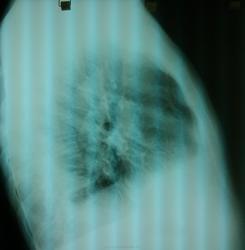

Пациент, 38 лет. Какие будут мнения, не зная анамнеза.

Поискал бы жидкость справа.

Пациентка оперирована. Танталловый шов справа в нижнем поле парамедиастинально

Предположу старые плевральные дела и свежий плеврит. Этиология, возможно, твс.

Плеврит,послеоперационные изменения.

Спасибо. Долго искал скобки я на прямом. Нашёл только потом, когда посмотрел боковой.) Поправлю Вас, расположение их далеко от парамедиастинального.) Параллельно нижнему краю 9-го ребра - это да.)

- Предположу старые плевральные дела и/или свежий плеврит. Этиология, возможно, твс.